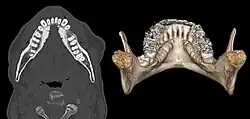

Torus mandibularis seen at axial CT and volume rendering

Torus mandibularis is a bony growth in the mandible along the surface nearest to the tongue. Mandibular tori usually are present near the premolars and above the location on the mandible of the mylohyoid muscle attachment.[1] In 90% of cases, a torus is on both inner sides of the mandible (left and right); however, they may differ in size.